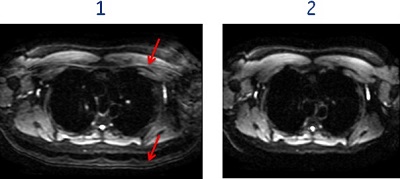

Figure 2. Real Time Center Frequency on/off affects on fat suppression

Table 1. Image legend Number Description 1 Image acquired with Real Time Center Frequency option turned Off. The arrows indicate the area of poor fat suppression.

2 Image acquired with Real Time Center Frequency option turned On. Note the improved fat suppression. - To reduce signal drop-off in areas of high B0 inhomogeneity (off-isocenter, or area with high tissue susceptibility).